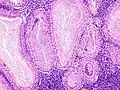

Bajo el microscopio, el tumor de Warthin tiene una apariencia muy característica. Se ven los espacios quísticos rodeados por dos hileras uniformes de células acinares con núcleos centrales y picnóticos. Estos espacios quísticos tienen epitelio que lleva el nombre de proyecciones papilares que protruyen hacia los espacios quísticos. El epitelio en cuestión está compuesto en parte por un rico estroma linfoide con formación germinal en el centro.[4]

Histopatología del tumor de Warthin en la glándula parótida.

Otra vista de la imagen anterior.

Mayor magnificación de la imagen anterior.